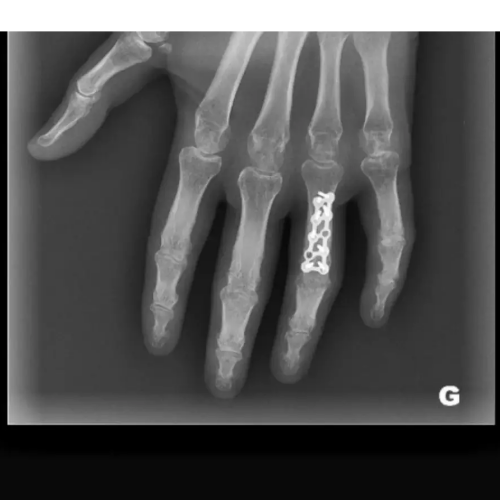

- fractures